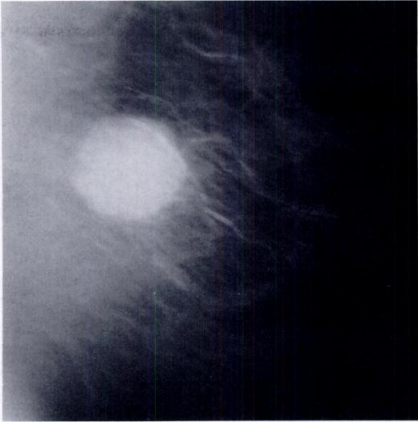

Κατηγοριοποίηση κακοηθειών Bi-rads

Αυτά τα κρίσιμα επιτεύγματα οδήγησαν στην ανάγκη κατηγοριοποίησης των βλαβών του μαστού και στη δημιουργία του συστήματος αναφοράς και δεδομένων απεικόνισης μαστού (bi-rads), το 1993, το οποίο έχει πλέον φτάσει στην 5η έκδοσή του. Το bi-rads βελτίωσε την επικοινωνία μεταξύ των χειριστών σχετικά με τις βλάβες των μαστών. Τα ευρήματα απεικόνισης μαστού χωρίζονται σε 7 κατηγορίες, από 0 έως 6. Η κατηγορία 0 υποδεικνύει την απουσία μη φυσιολογικών ευρημάτων και η κατηγορία 6 αντιπροσωπεύει κακοήθεια που έχει αποδειχθεί με βιοψία.